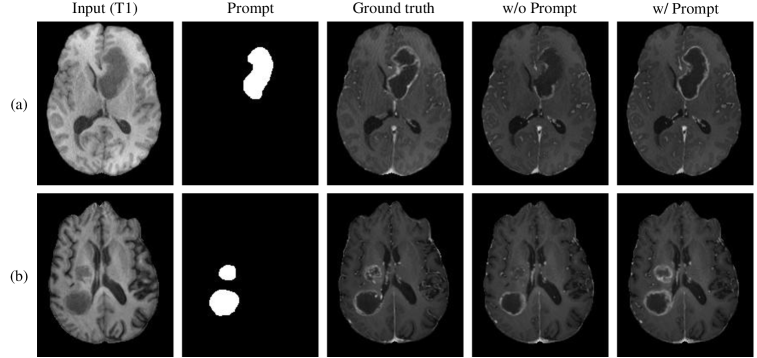

Refer to caption

Figure 5: The effect of prompts is demonstrated when handling complex tumor shapes.

Interactivity plays a crucial role in enhancing the performance of our model. As shown in Figure 5, the use of prompt information significantly improves the handling of more complex tumors. In case (a), when no prompts are provided, the model struggles to accurately delineate the complex contours of the tumor. However, when an experienced radiologist manually marks the shadow regions on the T1 image and inputs them as prompts into the network, a notable improvement in the generated results is observed. In case (b), when handling multiple lesions, capturing all of the lesions proves to be challenging. We suspect that this issue arises from data imbalance, as cases with multiple lesions are relatively rare. In this situation, radiologists can mark all suspicious areas to assist the generation process. The newly generated results, in turn, successfully capture all lesions without any omissions.